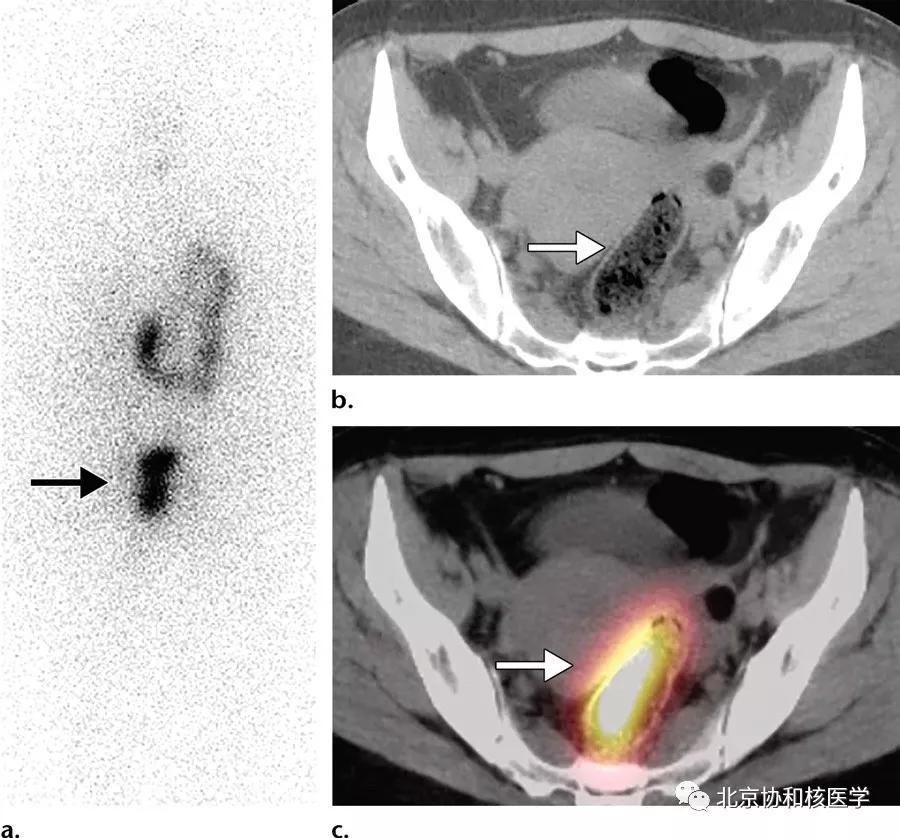

36岁女性,乳头状甲状腺癌甲状腺全切除术后,碘131治疗后7天显像见子宫内膜区摄取,考虑为碘在经血中滞留所致:

39岁女性,恶性卵巢甲状腺肿病史,行右侧卵巢切除术、甲状腺切除术、碘131治疗,碘扫可见残余甲状腺摄取、盆腔转移灶摄取及肝转移灶摄取: